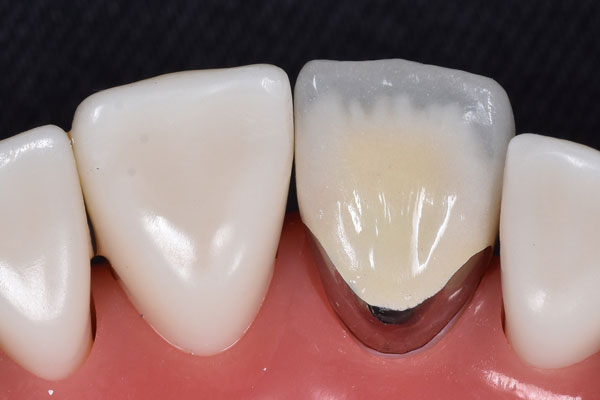

インレー・クラウン症例

治療前

治療後

治療期間 4回(1ヶ月)

費用 ・ハイブリッドセラミック

インレー2本

・オールセラミッククラウン1本

合計:143,000円

治療リスク・副作用 ・詰め物、被せ物をする時は自分の歯を削ることになります

・歯ぎしり・食いしばりが強い方は、セラミックが割れてしまうことがあります。